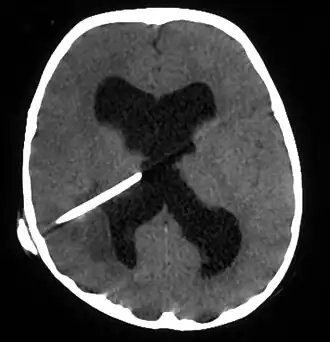

![]() Absceso cerebral en una persona con una derivación de LCR. El absceso es la región gris más oscura en la parte inferior izquierda de la imagen (que corresponde al lóbulo parietal derecho). Los ventrículos laterales son visibles en negro en el centro del cerebro, adyacentes al absceso.[1] | ||